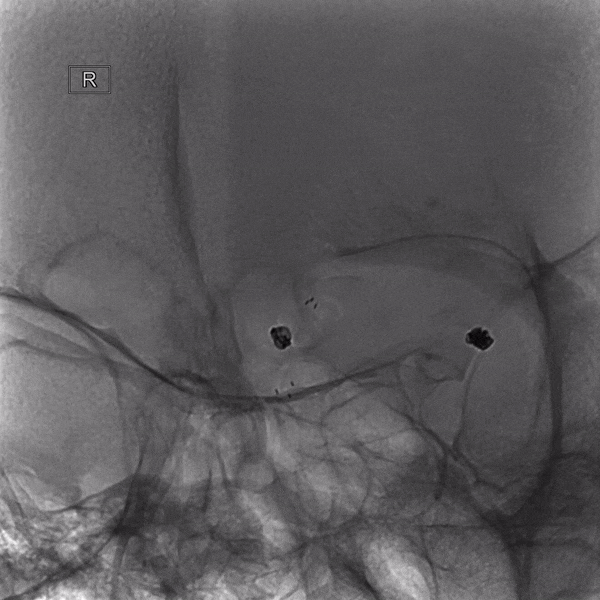

栓塞微导管及支架导管到位

强生 2mm*4cm

支架(Atlas 3.0*15mm)半释放,微创神通 1mm*1cm未解脱

造影提示右侧A1动脉闭塞

回收弹簧圈、回撤栓塞微导管、支架全释放及使用替罗非班等处理

经处理后,载瘤动脉复通